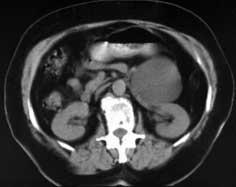

Пациент 30лет. 3 года болеет панкреатитом. Последнее обострение около месяца назад. Поступил с температурой 38,5, умеренными болями в эпигастрии и левом подреберье. На УЗИ и КТ визуализируются сообщающиеся друг с другом жидкостные образования в парапанкреальной клетчатке. Хорошо выражена пиогенная капсула, что позволяет однозначно утверждать что это абсцессы (3-х камерный абсцесс). На некоторых сканах камеры абсцесса обозначены стрелками.

Пациент 30лет. 3 года болеет панкреатитом. Последнее обострение около месяца назад. Поступил с температурой 38,5, умеренными болями в эпигастрии и левом подреберье. На УЗИ и КТ визуализируются сообщающиеся друг с другом жидкостные образования в парапанкреальной клетчатке. Хорошо выражена пиогенная капсула, что позволяет однозначно утверждать что это абсцессы (3-х камерный абсцесс). На некоторых сканах камеры абсцесса обозначены стрелками.